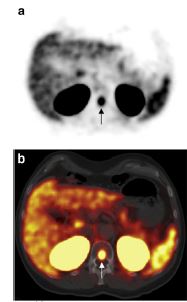

68GA_PSMA2